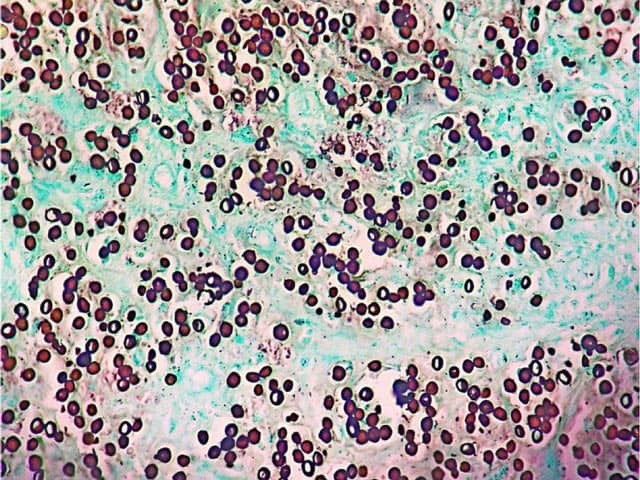

The diagnosis is made on clinical suspicion and direct microscopic examination. Skin biopsy is the gold standard for diagnostic confirmation; visualisation of the fungal forms are best obtained with the use of silver or periodic acid-Schiff (PAS) stain.

Grocot staining of lobomycosis showing oval yeast-like bodies